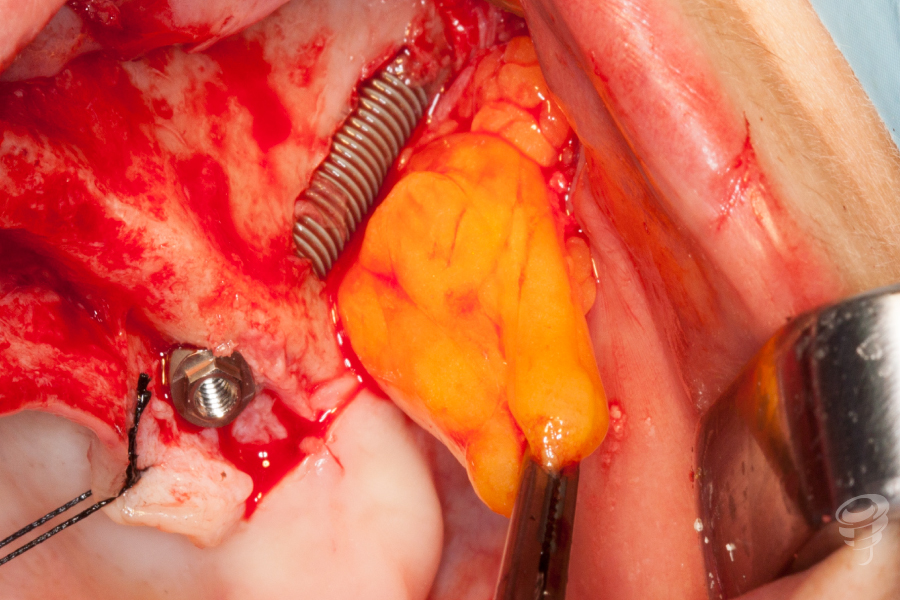

En este sentido quiero hacer énfasis en dos aspectos. Por un lado, la «externalización» del cuerpo del implante puede aumentar el riesgo de complicaciones en los tejidos blandos por la aparición de dehiscencias y exposiciones, por lo que suelen asociarse técnicas que reduzcan este riesgo (como técnicas de regeneración ósea o el uso de la bola de Bichat) (Imagen 50-53) al tiempo que necesitamos disponer de implantes con el cuerpo mecanizado, que tengan buen comportamiento biológico en caso de exposición. (Imagen 54)

- Interposición del colgajo de bola de Bichat entre el implante y la mucosa para reducir el riesgo de exposición. (Imagen 51-52)